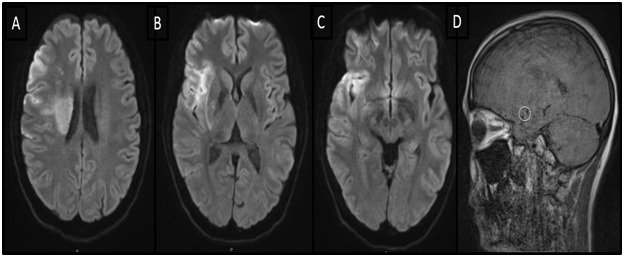

Clinically the patient improved on the table and was able to raise the left hemibody against gravity (MRC grading for muscle strength=4), we noticed complete resolution of the gaze deviation and improved dysarthria. A follow up CT head was performed on the day 1 (Figure 3). The patient was discharged home with outpatient rehabilitation and NIHSS=2.

Figure 3 Computerized tomography (CT) head demonstrating intracranial stent in the right M1 segment of the middle cerebral artery, on day 1.